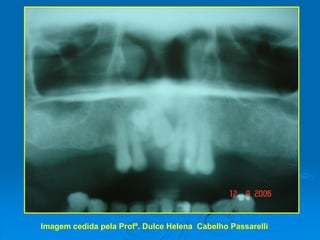

ODONTOMA COMPOSTOImagem cedida pela Profª. Dulce Helena  Cabelho Passarelli